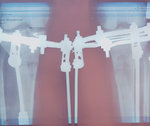

Дата операции 15.03.2017г.

Дата снятия аппаратов 23.06.2017г.

Срок лечения 97 дней.